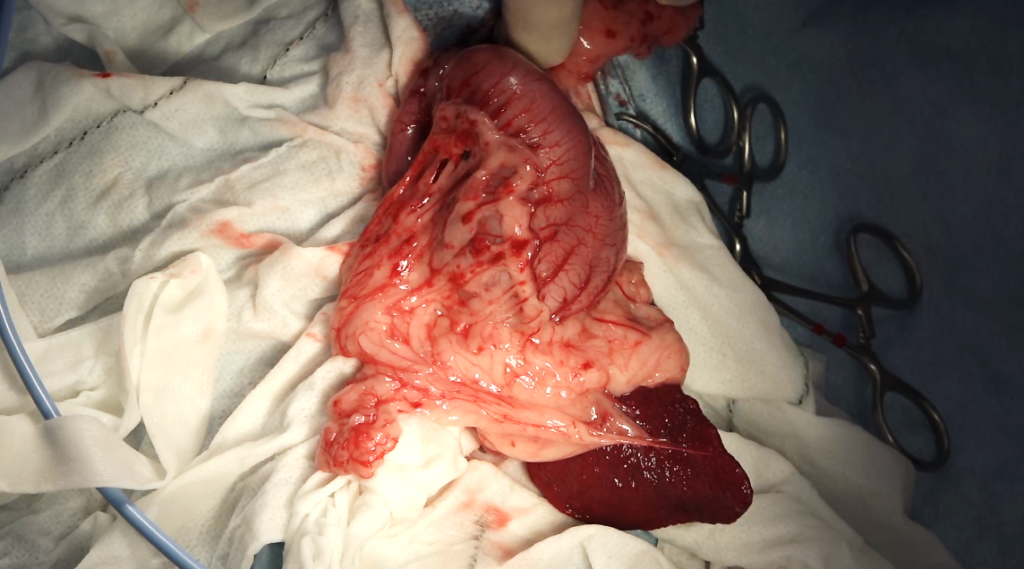

開腹下に消化管を確認したところ、胃から十二指腸にかけて連続するひも状の異物を触知しました。異物は軟性であったため慎重に胃内へ戻し、胃切開によって毛球を摘出しました。胃内には他にも毛球が認められ、あわせて摘出しました。